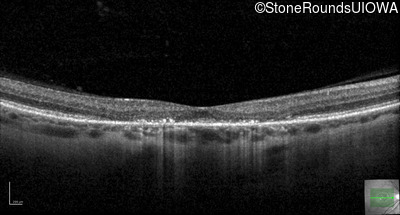

Age at visit: 40 years

OD OS

This 40 year old woman first noticed a reduction of her visual acuity about two years ago. She has been sensitive to light for as long as she can remember.

Diagnosis & molecular findings

Disease Gene Allele 1 variant(s) Allele 2 variant(s) Inheritance mode

AD Stargardt Disease PROM1 Arg373Cys CGC>TGC   AD